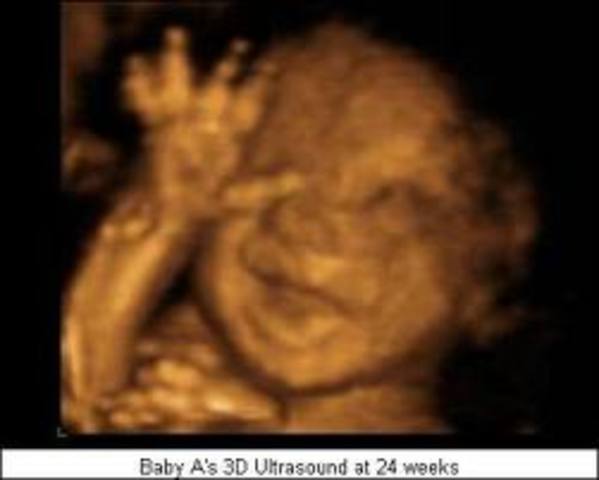

24 weeks

Your baby's growing steadily, having gained about 4 ounces since last week. That puts him at just over a pound. Since he's almost a foot long (picture an ear of corn), he cuts a pretty lean figure at this point, but his body is filling out proportionally and he'll soon start to plump up.